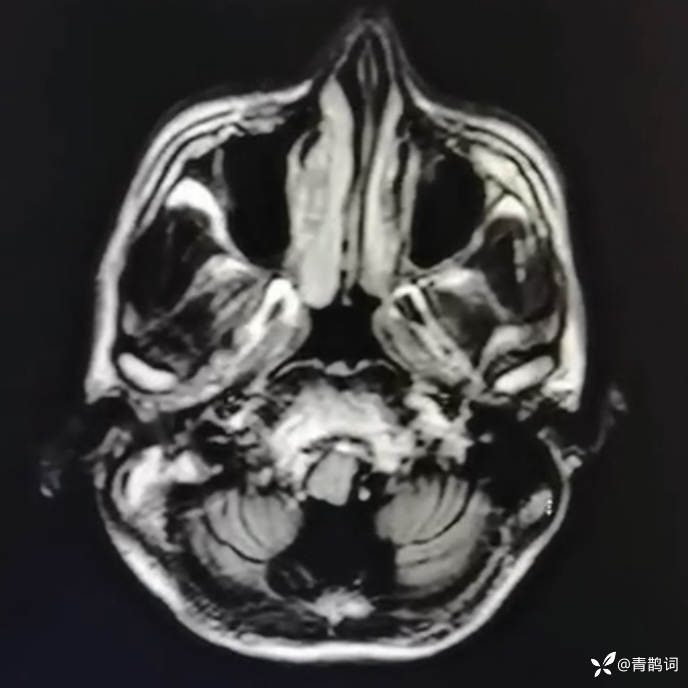

乐痴于医等 2人推荐简要病史:42岁男性,记忆力下降及听力下降一年余。既往体健,否认前驱感染病史。否认家族史。三个月前就诊于当地医院,自述腰穿脑脊液乳酸增高。现就诊于我院,查体记忆力下降,计算力下降,定时定向差,吟诗样语言。完善磁共振如下:

2.患者小脑萎缩严重,和大脑半球的病灶之间有无关系?能否用一元论解释?